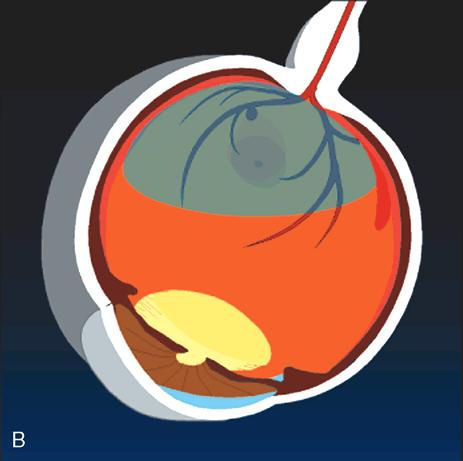

Nd-YAG laser photodisruption may be employed in special cases in which thick, fresh blood is trapped beneath the internal limiting membrane13 or behind the posterior hyaloid.14 Blood in these anatomic locations does not itself cause damage to the retina, but it may limit central vision, and it may prevent the clinician from identifying underlying retinal pathology. Photodisruption results in a localized concussive effect that breaks open the posterior hyaloid or internal limiting membrane. If the trapped blood has not yet solidified, it may then be allowed to “spill out” through the opening into the vitreous cavity (Fig. 5). Risks of this technique include damage to the underlying retina if the laser treatment is applied too close to the retina or if the blood is not thick enough to absorb the concussive effect.

Fig. 5. A. Illustration of a macroaneurysm with thick sub-internal limiting membrane (ILM) hemorrhage Because the hemorrhage obscures the macula, the patient's visual acuity is poor and it is not possible to determine clinically if the hemorrhage extends beneath the macula. Nd-YAG laser photodisruption can break through the ILM. B. If the blood has not yet solidified, it may drain through the laser opening and improve visual acuity and visualization of the macula.